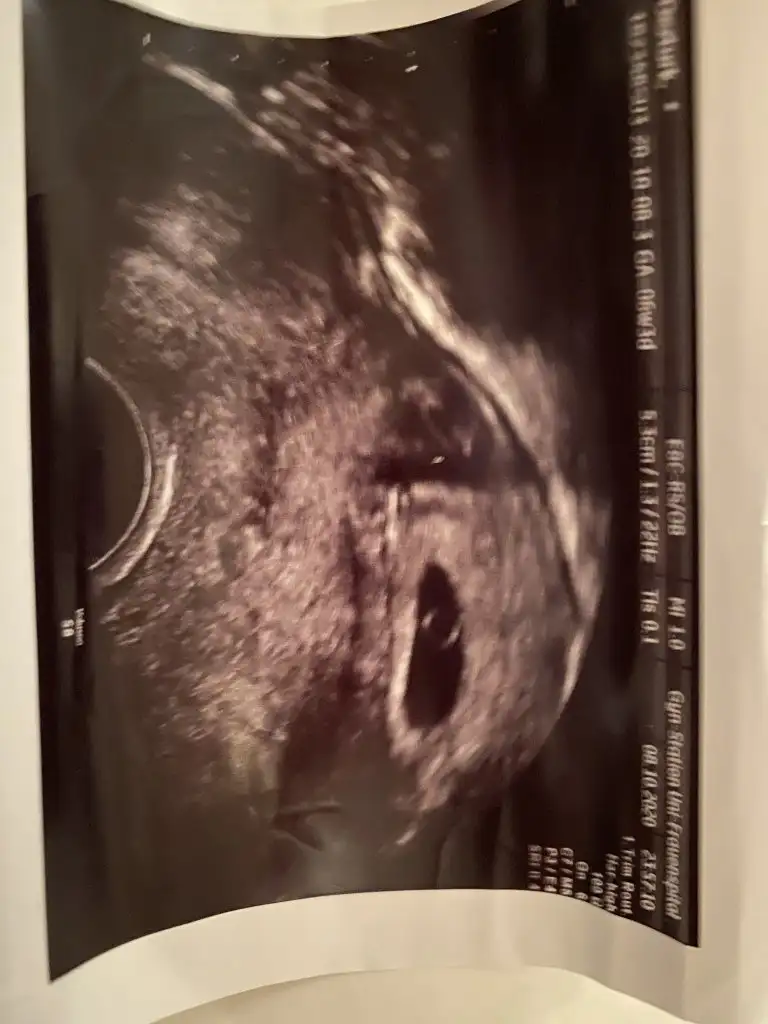

Bu arada 12. Haftada ki halimiz anlayan var mı ki bu arada konuyu açan benim kullanıcı adımı değiştim sadece

Karındansa kız vajinal ise erkek kaç haftalık burda 11 yada 12 haftada nub tahmini yaparım paylaşırsanız

Herkes sizin tahmin edebileceğinizi söylüyor lütfennnnn banada bir tahminde bulunurmusunuzz lütfennn 1. Gönderdiğim fotograf vajinal ultrason 6. Haftalarındaydı 2. Fotografta karından bakıldı 7. Haftalarındaydı hayırlısı neyse o olsun inşallahhhh ama çoooook merak ediyorum dört gözle cevabınızı bekliyorumLÜTFENNNNN